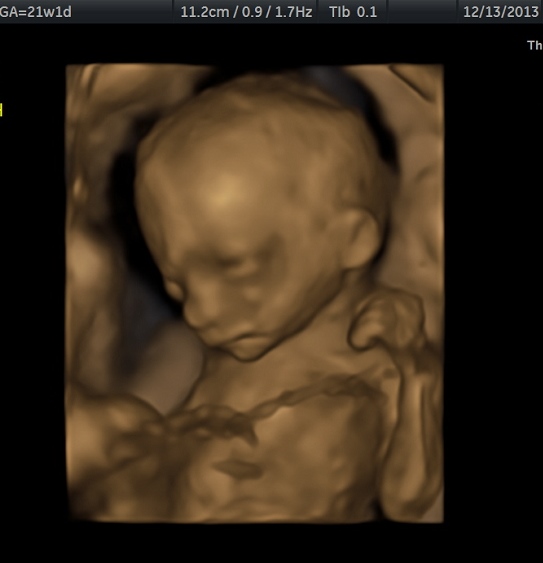

Updates? We had a great NT appt and the doctor and ultrasound tech made a prediction that we have identical girls. I am trying not to get too excited because it is still so early but I am excited about the prospect. They both loooked great at the scan. Measuring within 3 days of eachother. Baby A was really mellow and Baby B was bouncing all around.